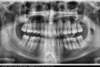

Important encombrement traité par gouttières

B-Début 2